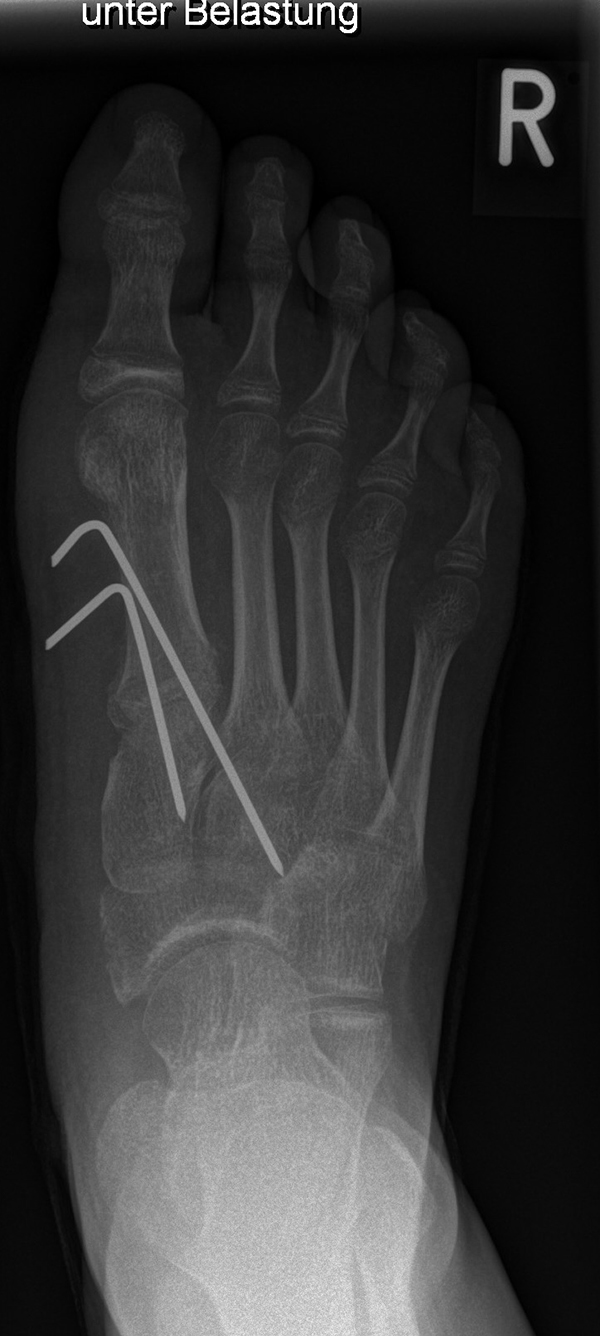

Die Indikation für eine inkomplette DMMO von dorsal Richtung plantar ist der Morbus Köhler II. Hier erfolgt eine dorsal extendierende retrokapitale Osteotomie mit verbleibender plantarer Kortikalis. Ein 1.4 oder 1.6 mm Kirschner-Draht wird in den Schaft von plantar eingeführt und das Köpfchen anschließend über einen Draht in eine verbesserte Gelenkkongruenz gedrückt und darüber gleichzeitig fixiert (Abb. 19).

Abb. 19 a-b: präoperative Diagnostik bei M. Köhler II (a) und postoperativer Verlauf nach minimaler Osteotomie und Köpfchenanhebung mit einem Draht (b).

Zum Lesen der Bildbeschreibung und zur Vollansicht bitte die Bilder anklicken. Bilder: A. Helmers.